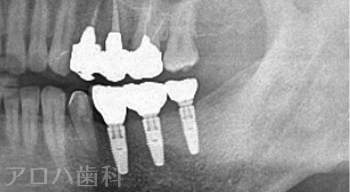

CASE01

初診時

治療終了後5年時

| 主訴 | 入れ歯をやり替えたい |

|---|---|

| 治療内容 | 上下顎とも状態が悪い歯を抜いて奥歯をインプラントで修復しました。 前歯は患者さまの希望のもとそのままにしています。 上顎は骨の高さが足りなかったため、【サイナスリフト】という特殊な手術を行い骨の高さを獲得しています。 術後経過もメインテナンスに通っていただいており、良好な状態を保っています。 |

| 治療期間 | 1年6ヶ月 |

| 治療費用 | 5,060,000円 |

| 費用詳細 | ・サイナスリフト(2か所) 660,000円 ・セデーション(静脈内鎮静法) 110,000円 ・TEC(仮歯) 220,000円 ・インプラント手術+アバットメント+上部構造(9歯) 3,960,000円 ・ポンティック(1歯) 110,000円 |